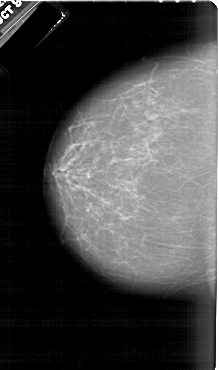

FILE: A_1950_1.RIGHT_CC.OVERLAY

TOTAL_ABNORMALITIES 1

ABNORMALITY 1

LESION_TYPE MASS SHAPE IRREGULAR MARGINS SPICULATED

ASSESSMENT 5

SUBTLETY 5

PATHOLOGY BENIGN

TOTAL_OUTLINES 2

BOUNDARY

CORE